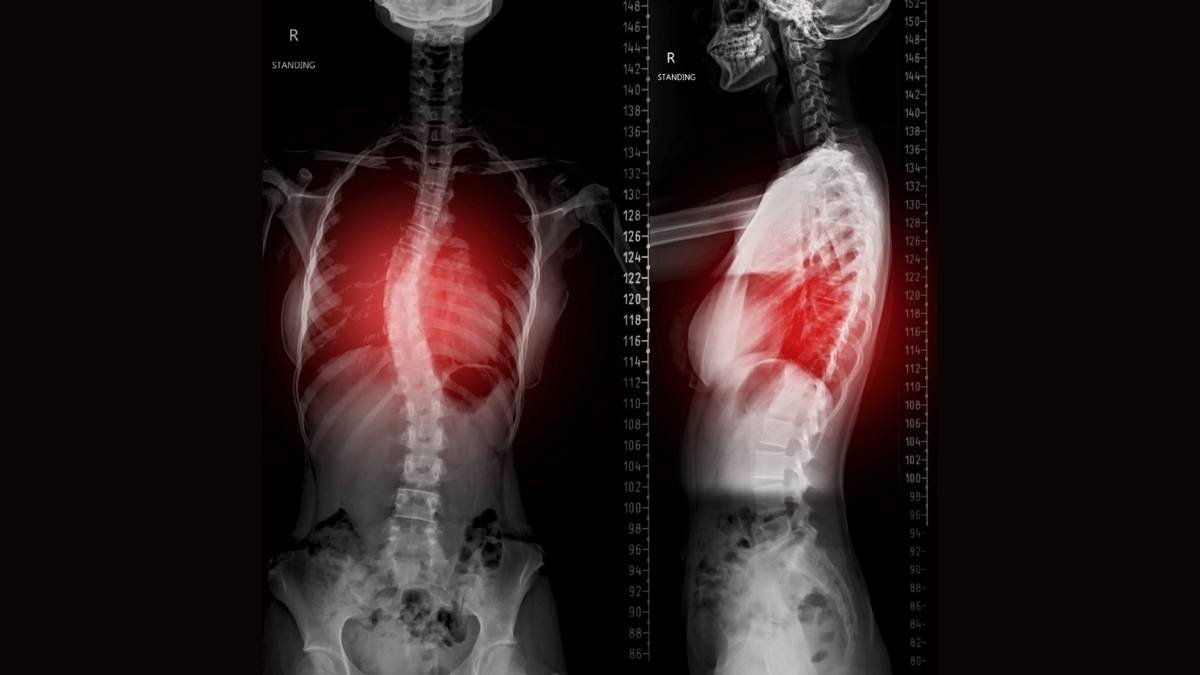

A escoliose idiopática do adolescente (EIA) representa uma das condições ortopédicas mais prevalentes entre jovens, afetando aproximadamente 2-3% da população adolescente mundial. Em Foz do Iguaçu, região de fronteira no Paraná, o acesso a tratamentos especializados como o Método Schroth em Foz do Iguaçu-PR tem se tornado uma realidade crescente, oferecendo alternativas não-cirúrgicas eficazes para pacientes com deformidades espinhais. Esta abordagem terapêutica tridimensional, desenvolvida pela fisioterapeuta alemã Katharina Schroth na década de 1920, baseia-se em exercícios específicos de correção postural e respiratória que visam a estabilização e melhoria das curvaturas escolióticas.

O Método Schroth fundamenta-se em princípios biomecânicos rigorosos que abordam a escoliose como uma deformidade tridimensional complexa. Esta abordagem consiste na correção tridimensional do padrão específico da curvatura do paciente usando uma combinação de exercícios sensoriomotores, posturais e respiratórios corretivos. A metodologia considera que cada padrão de curvatura escoliótica é único, exigindo um programa de exercícios personalizado que leva em conta as características anatômicas específicas do indivíduo.

A avaliação inicial em Foz do Iguaçu inclui radiografias panorâmicas da coluna vertebral, avaliação postural detalhada, teste de flexibilidade da curvatura, avaliação da função respiratória e questionários de qualidade de vida. Esta avaliação abrangente permite o desenvolvimento de um programa terapêutico personalizado que maximize os resultados potenciais do tratamento.